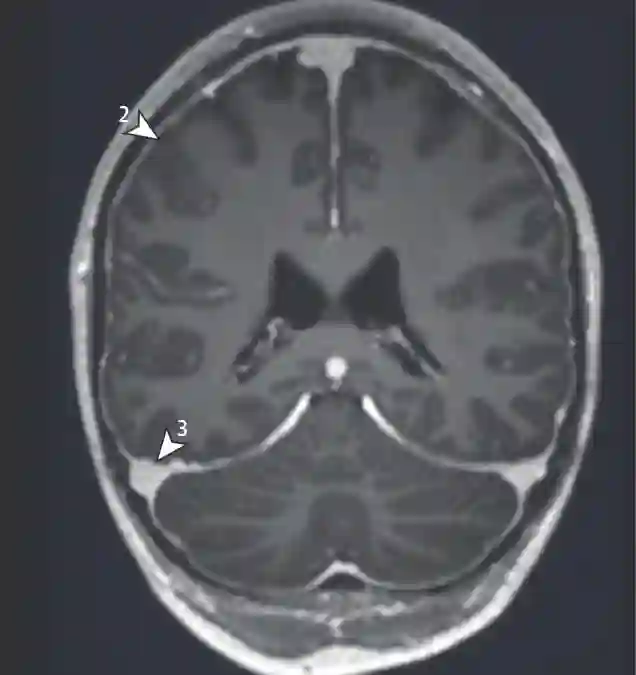

SIH Score

2) Pachymeningeale Enhancement 3) Vergrößerung der Sinus durae matris. Dobrocky T. et al. 2019. JAMA Neurology.